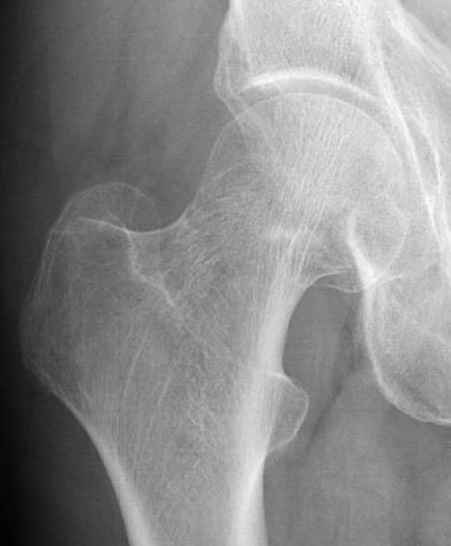

Почему неполный перелом? Я бы назвал его вколоченным!

Перелом конечно не вколоченный т.к. видно линию перелома и нет суперпозиции костной ткани.

Добрый день. Перелом коварный. Через время может произойти лизис в области "неполного" перелома и он превратиться в "полный" со всеми очевидными проблемами, тем более у пациента, склонного к питию. Если не разовьется делирий или после выхода из него, рекомендую внутренний остеосинтез винтами.

Профилактику дальнейшего раскола неполного перелома шейки провели тремя канюлированными шурупами.